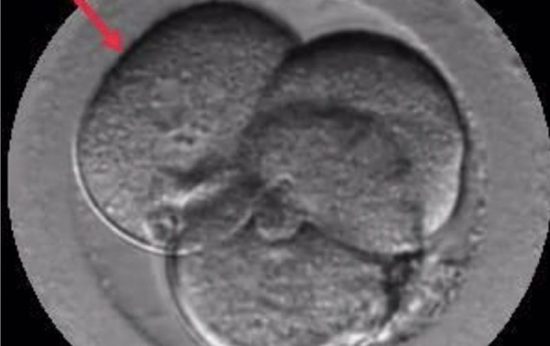

El Dr. Borja Marquès es el autor del estudio «Signos de auto-reparación de los embriones en el laboratorio de FIV» cuyas conclusiones apuntan que los embriones poseen un mecanismo de auto-corrección ignorado hasta hoy. Según este trabajo que se presenta esta semana en Murcia, en el 36º Congreso de la Sociedad Española de Ginecología (SEGO), embriones que han sufrido división reversa (desaparición de alguna de sus células) o multinucleación (presencia de dos o más núcleos en alguna de sus células) pueden acabar con éxito, es decir, con un embarazo normal y el nacimiento de un bebé sano.

Gracias a los incubadores con cámaras time-lapse (Embryoscope), en los laboratorios de Institut Marquès ha sido posible captar las imágenes de embriones con división reversa reabsorbiendo sus propias células y de embriones multinucleados expulsando las células anómalas en el 4º o 5º día de vida. Para conseguirlo, se ha analizado el desarrollo de 21.274 embriones, desde su fecundación hasta que llegaron a blastocisto.